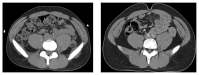

Retroperitoneal fibrosis (RPF) is a condition characterized by chronic inflammatory and fibrotic changes in the retroperitoneum that can lead to serious complications including kidney failure, mesenteric and limb ischemia, and deep venous thrombosis among others. Affected individuals may present with nonspecific symptomology that would require a high clinical index of suspicion for prompt diagnosis. We herein discuss a case of a young African-American man with recurrent deep venous thrombosis who presents with a 4-week history of constant aching pain of abdomen and back and kidney failure. Initial noncontrast computed tomogram (CT) only revealed mild bilateral hydroureteronephrosis with inflammatory changes but without obvious mass or lymphadenopathy. At the insistence of the renal consulting team to rule out RPF, a CT-urogram was performed which revealed an infiltrative mass encasing the aorta, inferior vena cava, and common iliac vessels. Laparoscopic biopsy revealed dense fibroadipose tissue, lymphocytic aggregates, focal scattered IgG4-positive plasma cells, and fibrin deposition. Patient underwent bilateral nephrostomy placement and empirical corticosteroid therapy with resolution of kidney failure. Our case illustrates a classic presentation of RPF with relatively benign findings on noncontrast CT that could have been missed if clinicians did not keep a high index of suspicion for the condition.